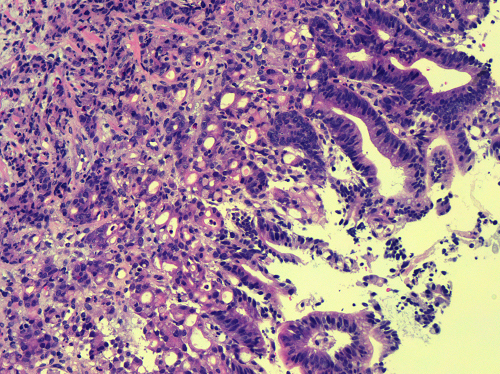

这才发生了最开始的一幕,血液科(肿瘤内科)医生电话联系到白先生去做胃镜。微创肝胆外科主任医师王永光在胃镜下为白先生取了4块活检组织再次送到病理科。病理科医生王丽宁在显微镜下认真审阅这份胃镜活检切片,最终明确诊断为胃癌。

▲胃体 HE 20X